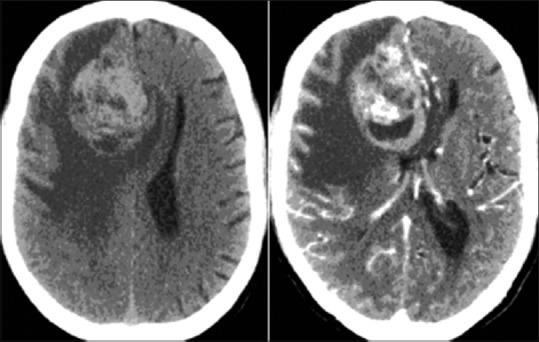

We present a rare case of the primary intracranial melanoma in the right parafalcine frontal region in a 65-year-old male. Computed tomography and magnetic resonance imaging showed a Space occupying lesion in the right parafalcine frontal region with necrosis, vasogenic edema and mass effect. A rather well-defined, dark brown-black tumor was totally removed and histologically diagnosed as malignant melanoma. The patient improved after surgery. In our case, no systemic melanomas were found in close clinical examinations, there was a single nodular tumor attached to the leptomeninges and a favorable outcome was obtained by surgical treatment alone. Primary central nervous system melanomas have rarely been reported, and this case is reported for its rarity.

我们报告了一例罕见的原发性颅内黑色素瘤病例,发生在一名65岁男性的右侧大脑镰旁额叶区域。计算机断层扫描和磁共振成像显示右侧大脑镰旁额叶区域有一个占位性病变,伴有坏死、血管源性水肿和占位效应。一个边界相当清晰的深棕色至黑色肿瘤被完全切除,组织学诊断为恶性黑色素瘤。患者术后病情好转。在我们的病例中,经过仔细的临床检查未发现全身性黑色素瘤,仅有一个附着于软脑膜的结节状肿瘤,仅通过手术治疗就取得了良好的效果。原发性中枢神经系统黑色素瘤鲜有报道,本病例因其罕见性而被报告。